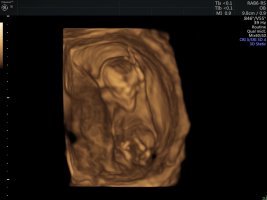

173,7 KB · Görüntüleme: 365

Merhaba, bizim cinsiyet hala kesinleşmedi 🙂 ben biraz nubu araştırdım. Ve size ilk gönderdiğim resimde nub kısmının dik olduğunu gördüm. Ama aynı anda verilen diğer görüntü aşağıda fakat burda da nubu paralel gözüküyor. Kafam karıştı açıkcası. Hangisi sizce?

Emin olmamakla birlikte kız gibi görünüyor canım umarım sağlıklı kucağına alırsın sonucu kesin öğrendiğinde de yazarsan sevinirim :hamis: :d040: